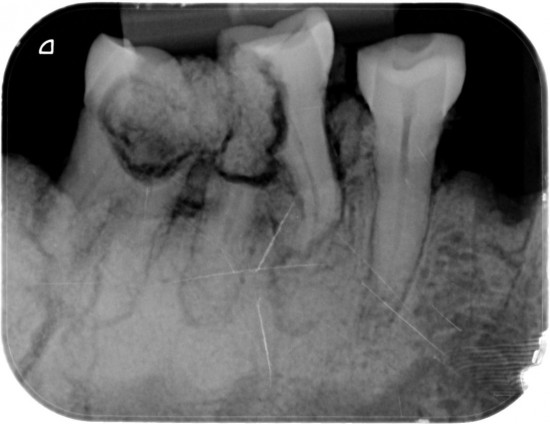

Van de M2 en de M1  (Links) werden  extra rontgenfoto,s gemaakt om  duidelijk te maken dat het niet een maar  twee aparte kiezen betrof .

Duidelijk zichtbaar de wortels van beiden tanden ..

Verder was goed zichtbaaar de vergaande  botontsteking bij de gebroken kiezen .